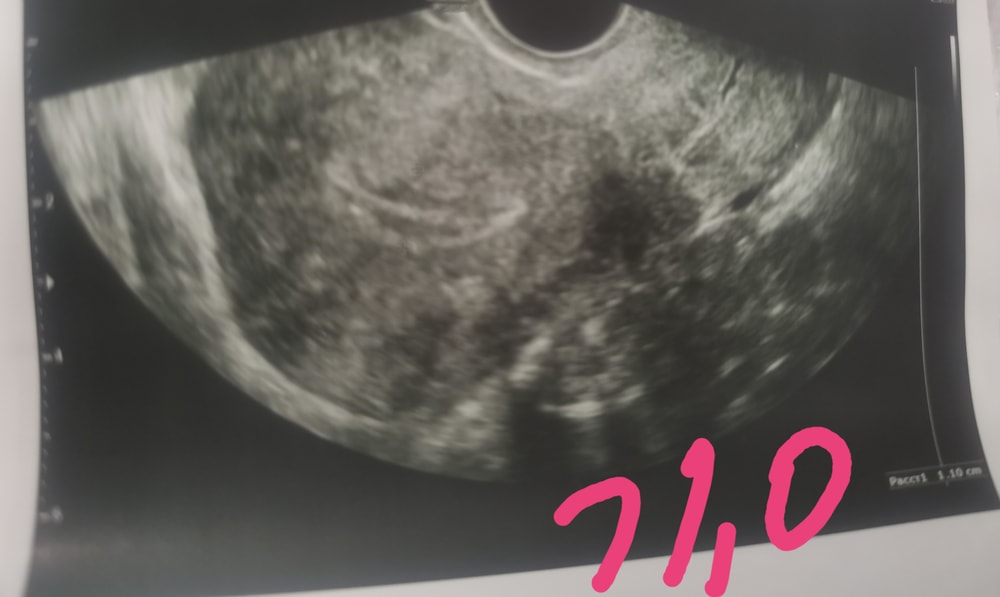

У меня в день пункции эндик был 11 мм, в день переноса 6.2 мм😱😱😱в день переноса добавили еще дивигель. Эндик от прогестерона просто уплотнился, а не сдулся. Структура была хорошая, трехслойный. Удачи вам!